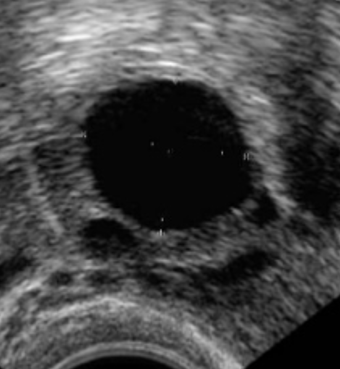

Figuur 2. Eierstok aan begin van de cyclus met kleine eiblaasjes en eierstok met dominant eiblaasje.